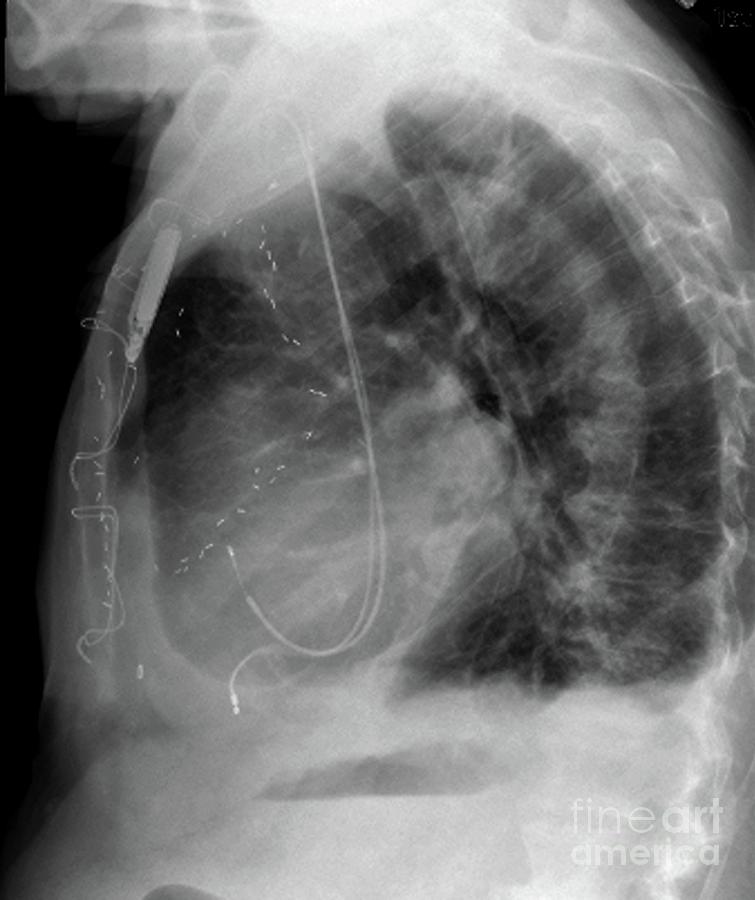

From fineartamerica.com

Pacemaker And Coronary Bypass Surgical Clips Photograph by Zephyr What Are Surgical Clips In An Xray The reason i ask is there is meant to be a small amount of nickel in titanium. Refer to the article on medical devices in the abdomen and pelvis for a view. If you google your very own topic title word for word. These devices are a common cause of artifacts and may trip the unweary, but in general, are. What Are Surgical Clips In An Xray.